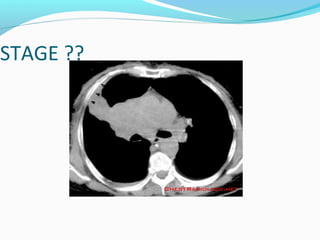

STAGE ??